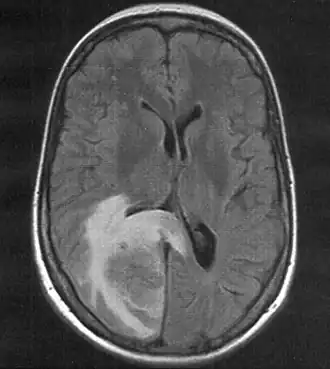

Skull MRI (T2 flair) of a brain metastasis with accompanying edema